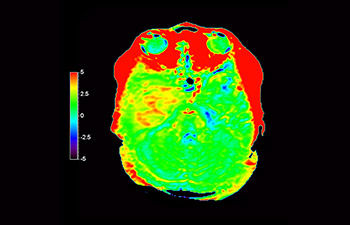

Glioblastoma recurrence

Brain imaging for glioblastoma recurrence

with 3D APT